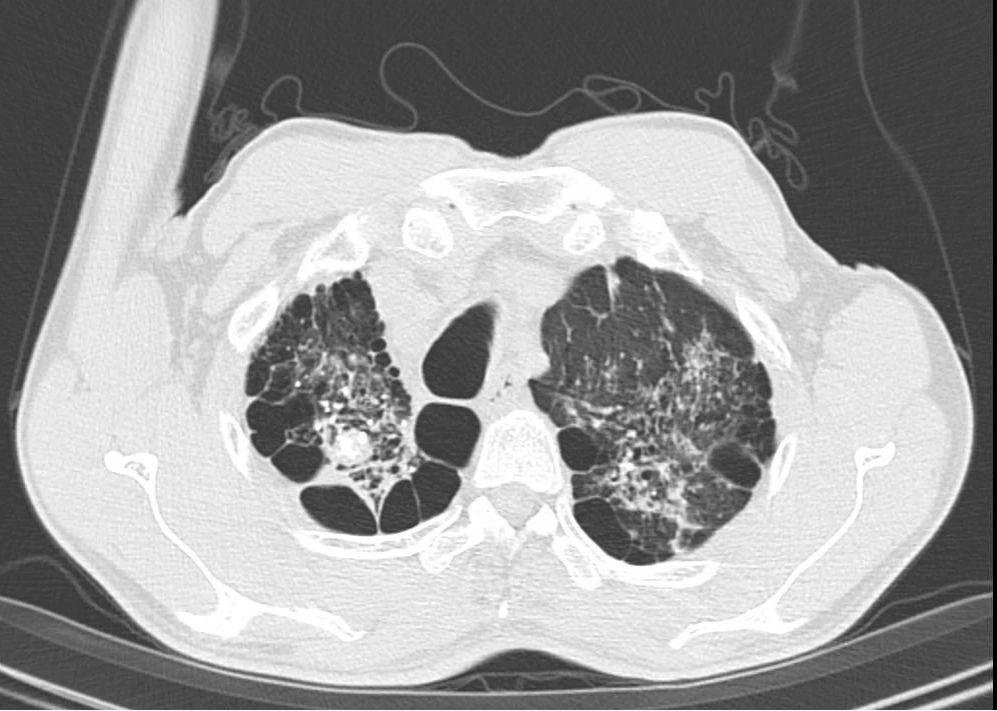

“来到医院时,患者不停地喘气。通过CT检查,发现他两侧的肺组织都长着像鱼泡一样的结构——被称为‘肺大泡组织’。”胸外科主任刘文粤说,患者右肺肺大泡相互融合,较大的约14.4cm*8.1cm,合并肺气肿及胸腔粘连。

陈旧性肺结核多发肺大泡

融合形成巨大肺大泡